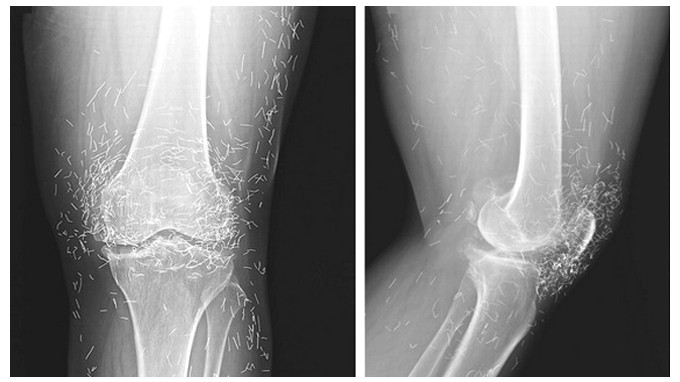

Phim chụp X-quang cho thấy, đầu gối của người bệnh có hàng trăm kim châm cứu bằng vàng

TPO - Các bác sĩ tại Đại học Boston vô cùng sốc khi phát hiện hàng trăm chiếc kim châm cứu trong đầu gối của một phụ nữ 65 tuổi người Hàn Quốc sau khi chụp X –quang. Bà cho biết trước đây đã châm cứu để chữa bệnh xương khớp.

Người phụ nữ này vào viện với triệu chứng đau gối dữ dội và được các bác sĩ chuẩn đoán viêm khớp nên cho bà chụp X-quang. Họ đã rất sốc khi phát hiện ra hàng trăm chiếc kim vàng trong đầu gối của bệnh nhân.

Người bệnh cho biết, trước đó đã tiến hành châm cứu. Châm cứu vốn là một biệt pháp chữa bệnh tốt, trong trường hợp này các bác sỹ phỏng đoán người tiến hành châm cứu đã cố tình để lại các kim châm cứu bằng vàng trong các mô để làm giảm đau cho bệnh nhân. Nhưng thực tế việc để lại kim châm hay bất kỳ một vật nào khác trong cơ thể người đều không phải là một ý tưởng tốt vì nó gây ra một loạt hệ quả.